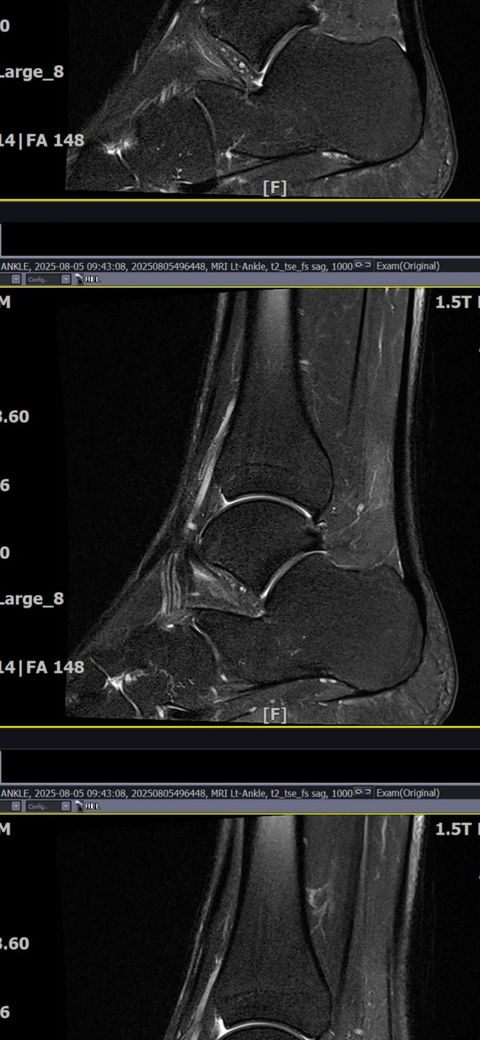

발목인대 상태 질문드립니다. (mri사진 첨부)

그래도 통증이 남아 8월 5일에 MRI를 촬영했는데, 병원에서는 “인대는 이어져 있고, 이 정도면 재활운동으로 호전될 것”이라는 설명을 들었습니다.

MRI 상 전거비인대와 발목 상태가 정말 회복 단계인지, 아니면 만성으로 넘어가는 건 아닌지 전문가분들의

의견을 듣고 싶습니다.

• 2번 째 사진

올려주신 mri를 보면 전거비인대는 연속성이 유지되고 있고 파열이나 큰 손상 흔적은 없어 재활로 회복 가능한 상태로 보입니다 다만 3개월 가까이 활동 시 통증과 미열감이 남아 있는 것은 조직 회복이 아직 완전히 끝나지 않았거나 주변 연부조직 관절 움직임 제한 등으로 인한 과민 반응일 수 있습니다.

초음파와 비교하면 mri 상으로 인대 연속성이 확인되므로 심각한 악화나 재파열은 아닌 것으로 판단됩니다

MRI상에서는 인대의 회복이 이루어지고 있는 덧으로 보이지만 인대의 회복은 소요되는 시간이 오래 걸리고, 주변 근육의 약화나 기능 저하로 인해 통증이나 불편감이 지속될 수 있습니다.